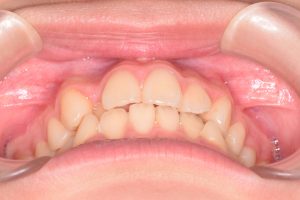

この患者さんは、初診時12才女性。

「上の前歯の中心がずれている」

「全体的に歯並びが良くないのが気になる」

ということで来院されました。

1期治療開始時(2024年3月)

2期治療開始時(2024年11月)

保定開始時(2025年1月)の写真です。

正面